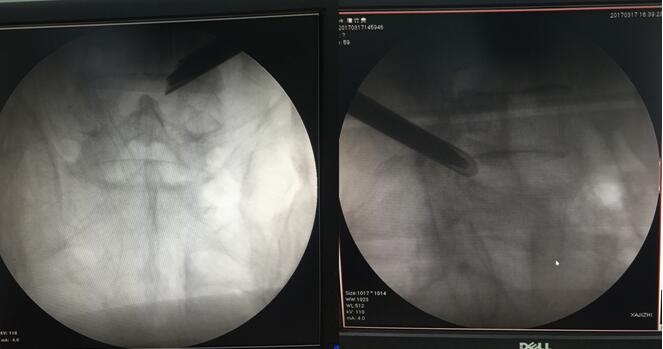

入院后,脊柱科湯偉副主任醫(yī)師詳細(xì)了解唐師傅的病情,根據(jù)腰椎磁共振、CT等檢查結(jié)果,發(fā)現(xiàn)唐師傅多節(jié)段腰椎間盤突出,且L4/5節(jié)段突出最多,引起患者典型的神經(jīng)根受壓癥狀,屬于責(zé)任椎間隙,明確診斷。且了解到唐師傅的家庭情況后,脊柱科醫(yī)生團(tuán)隊決定盡早為他安排手術(shù)。

唐師傅腰椎影像學(xué)檢查

3月17日,唐師傅成功進(jìn)行了局麻下椎間孔鏡下L4/5椎間盤微創(chuàng)摘除術(shù)。手術(shù)過程中,唐師傅明顯感覺左下肢疼痛及麻木癥狀減輕,術(shù)后第二天,唐師傅在戴腰圍帶的情況下,就可以下床活動,并感覺雙腿行走有力,穩(wěn)健。

術(shù)中手術(shù)通道置管